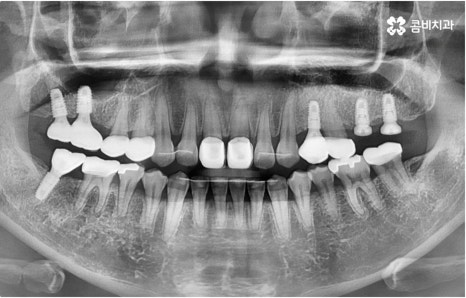

임플란트는 유치, 영구치 이후로 제 3의 치아라고 불리울 만큼 자연 치아의 상실에 대처하는 인공 치아 중에 가장 각광을 받고 있습니다. 저작력 회복이 80%에 가깝고 심미적으로 자신의 치아와 거의 다름없어 보이는 부분에서도 만족도가 높아 많은 분들이 찾고 있지만 식립 성공률과 안정적인 지속률에 크게 영향을 주는 올바른 위치 및 각도로의 식립을 무리하지 않게 진행하기 위해 술자의 높은 숙련도를 요하는 고난도의 수술이기 때문에 임상 경험이 많고 뛰어난 노하우를 갖추고 있는 담당의 선생님과 함께 하시는 것이 중요한 포인트라고 할 수 있어요.

환자분들의 상황에 따라 하루 만에 식립 및 임시 치아 장착까지 끝나서 바로 식사를 할 수 있는 원데이 임플란트 과정, 정밀 검사 후 디지털 장비를 이용하여 모의 수술 후 맞춤 가이드를 따라 무절개 / 최소절개 수술을 진행하는 네비게이션 임플란트 과정 등 관련 기술이 점점 더 섬세하게 발달하고 있어서 보다 편안한 이용이 가능하게 된 것은 사실이지만 본래 자신의 치아보다 좋은 인공 치아는 없을 것이기 때문에 건강할 때 이를 잘 유지 관리하고 구강 질환이 발생했을 때는 되도록 빠르게 이에 대처하실 필요가 있어요.